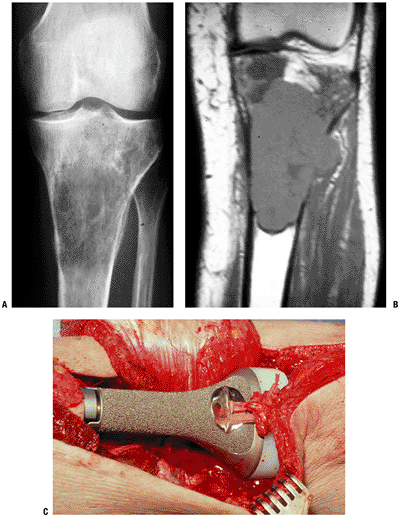

Difficult to achieve unionIntercalary allograft more common for iliofemoral fusion Allograft-prosthetic composite Best potential functional outcome Extremely high risk: instability, allograft fracture, allograft-host nonunion, infection Cement cup into allograft acetabulum Saddle prosthesis Stable hip but preservation of some motion May dislocate from iliac notch Mersilene tape through drill holes in ilium often used to increase initial stability  Figure 4.3-17 A proximal femoral Ewing sarcoma (A) was treated with neoadjuvant chemotherapy followed by resection and reconstruction with a proximal femoral prosthesis (B). (C) Intraoperative photos show the prosthesis in place with the bipolar component reduced in the acetabulum. (D) Figure 4.3-17 A proximal femoral Ewing sarcoma (A) was treated with neoadjuvant chemotherapy followed by resection and reconstruction with a proximal femoral prosthesis (B). (C) Intraoperative photos show the prosthesis in place with the bipolar component reduced in the acetabulum. (D)

Sutures attached to the remaining hip abductors proximally and to the

vastus lateralis distally have been pulled in the direction of closure.

When possible, these structures are reefed together and may be attached

to the prosthesis with tape or nonabsorbable suture.P.77Table 4.3-6 Common Reconstructive Options for the Proximal FemurReconstructive Option Advantages Disadvantages Unique Issues Allograft-prosthetic composite Allows reattachment of hip abductors